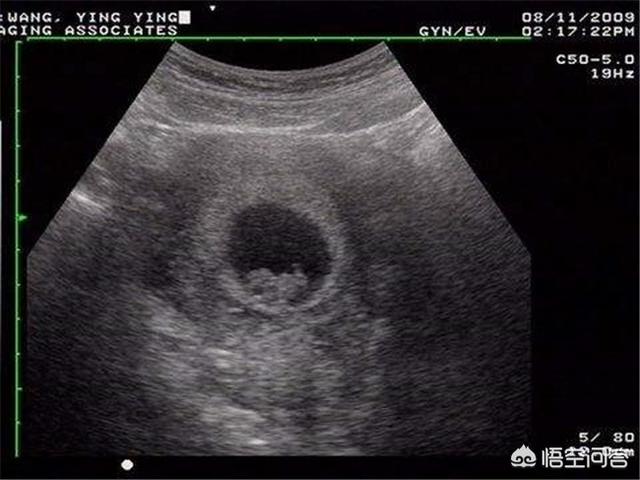

B超音波検査は一般的に胎児の発育と胎盤の位置をチェックするもので、胎児の病気の問題に関わることはほとんどありません。 4D超音波検査だけが胎児の奇形をスクリーニングするものなので、あなたが質問しているのはB超音波検査ではなく4D超音波検査のはずです。

4D超音波検査は、Bスキャン超音波検査の拡張版であり、胎児の奇形、胎児の顔や体の器官、四肢の奇形、例えば、胎児の口唇裂、合指症、四心室、内臓外反などを検出することができる。

妊娠中の4D超音波検査は、胎児の先天性心疾患、水頭症、口唇口蓋裂、四肢の発育をチェックすることができます。4D超音波検査では、母体内の胎児の動く画像も見ることができる。

超音波(4D超音波)は妊娠検査に必要なもので、主に胎児の体表や様々な臓器に奇形がないかをスクリーニングする役割を担っています。例えば、胎児の心臓、脳、腎臓、その他の部分の病気などです。

近年人気の超音波検査法である4D超音波検査を挙げる回答が多かった。 胎児の姿をより鮮明に見ることができ、母親や父親になる人に喜びや楽しみを与えるだけでなく、ビデオや写真を記録して記念に残すこともできる。

しかし実際には、4D超音波検査は通常の超音波検査に比べて診断効果を向上させるものではなく、一般の公立病院では4D超音波検査プログラムは実施されていない。

3Dか4Dかは超音波検査の結果に影響する要素ではなく、超音波検査医の経験が最も重要な要素です。